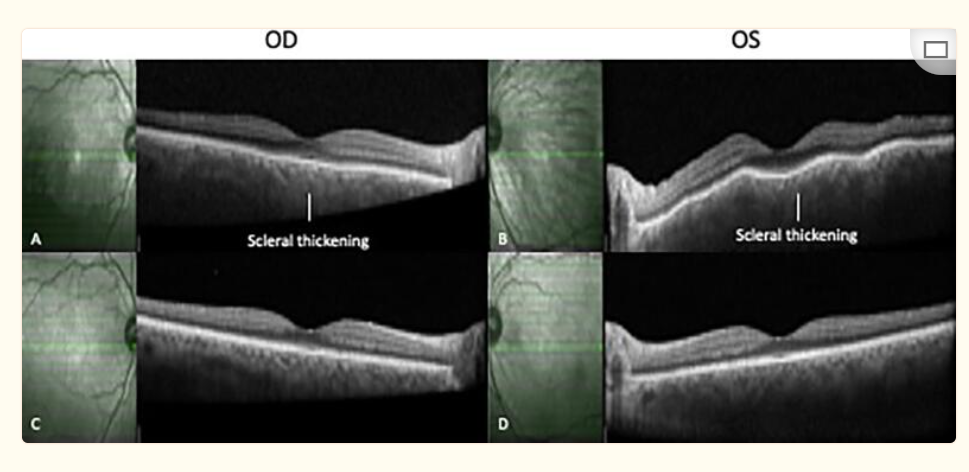

图2. 光学相干断层成像。A和B分别显示右眼和左眼初次就诊时的巩膜增厚;服用糖皮质激素两周后,C和D表现出明显改善。

图片